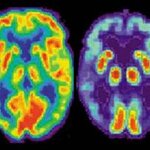

I had a "driveway" moment today listening to NPR - you know, where the story is really interesting and you've arrived at your destination but want to hear the end and folks walking by your car stare at you like you're about to pull off a drug deal? Anyway, the National Institute on Aging and the Alzheimer's Association announced the first new diagnostic criteria for Alzheimer's in about 25 years - the last diagnostic criteria were released in 1984. In brief, cases of Alzheimer's (arguably the most famous type of dementia) are growing exponentially. There are some rudimentary ways to "…